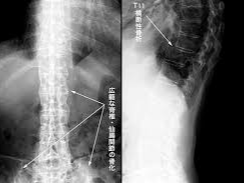

- 영상 검사: 엑스레이나 MRI를 통해 척추와 천장관절의 염증 및 손상을 확인합니다.

초기에는 영상검사상 이상이 뚜렷하게 나타나지 않을 수 있으므로, 증상이 지속된다면 반복적인 추적 관찰이 필요합니다.